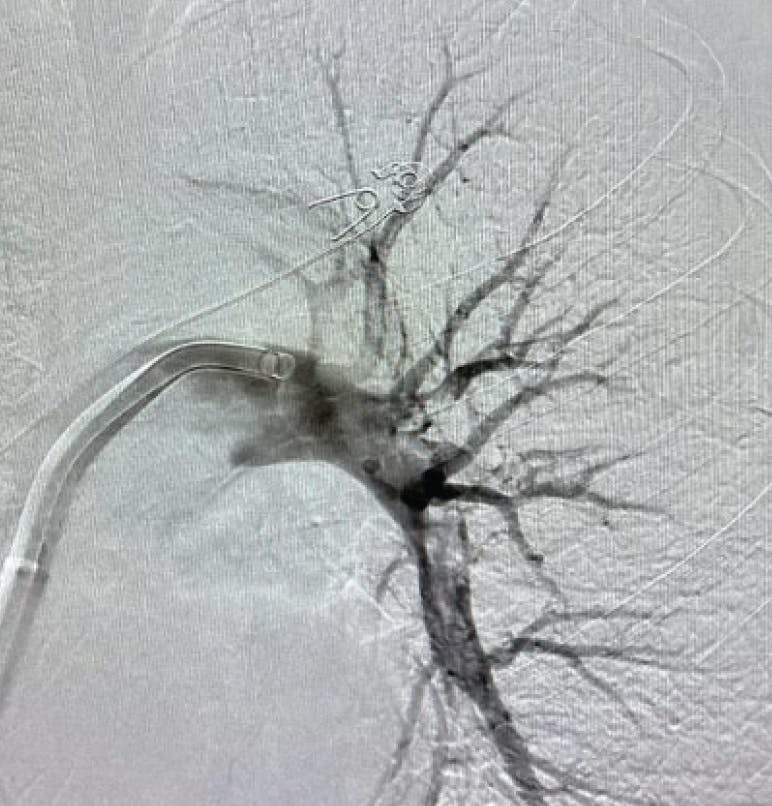

Figure 1. Initial angiogram of right PA

Based on the patient’s lab results, they were placed at the intermediate-high-risk category for pulmonary thromboembolism and, subsequently, the decision was made to pursue CAVT with Lightning Flash.

INTERVENTION

Access was achieved in the right CFV. Initial diagnostic testing revealed a PA pressure of 53/28 mm Hg. The 16-F Lightning Flash device was advanced into the right PA, and the flow switch was turned on to deliver continuous aspiration to the thrombus (Figure 2). By the conclusion of the case, there was complete resolution of thrombus and an EBL of < 200 mL. Postprocedure PA pressure was 38/17 mm Hg (Figure 3 and Figure 4). The patient experienced immediate clinical improvement in oxygen saturation and HR as well as resolved shortness of breath following the intervention.

Figure 2. Preprocedural venogram.

Figure 3. Post-thrombectomy angiogram.